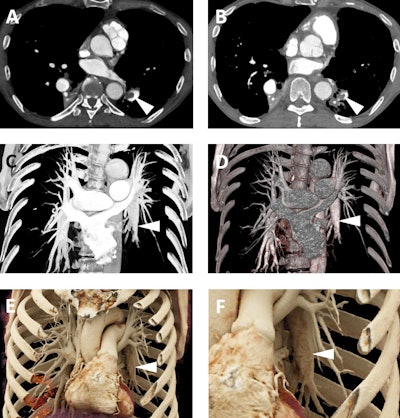

Images from an 87-year-old woman who presented for follow-up of mild aneurysmal dilation of the ascending aorta. A: Axial postcontrast 2D CT image demonstrates dilated vascular structures in the mediastinum (white arrowhead). B and C: Volume-rendered images demonstrate another of these dilated vascular structures (white arrowheads), which in 3D are more apparently aneurysms of the bronchial arteries. D-F: Cinematic-rendered images again demonstrate the multiple bronchial artery aneurysms (white arrowheads depict the aneurysm that arises at the origin of one of the bronchial arteries from the descending aorta). This patient was not felt to be a candidate for any therapy of these lesions given significant comorbidities, and no cause for the bronchial artery aneurysms was ever uncovered. Nonetheless, the realistic shadowing provided by cinematic rendering and that is most apparent in F provides very clear representation of the relationships between the aneurysms and other structures, including the heart and descending aorta, and would be of value in surgical planning.